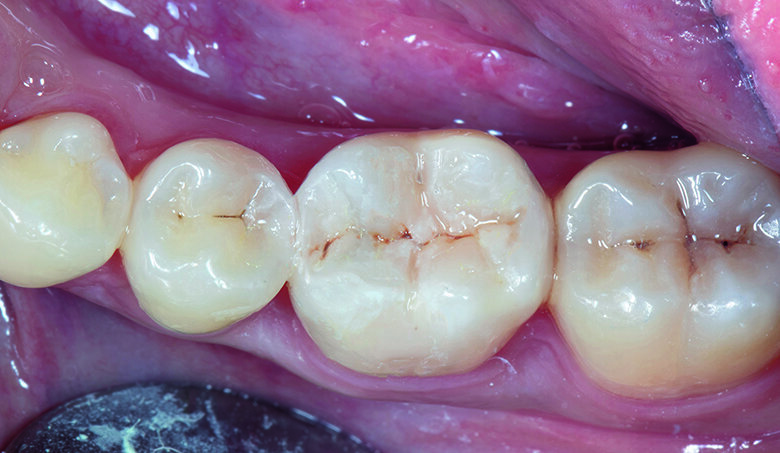

Fig. 13. After treatment - immediate post-op.

Fig. 14. Post-op after 7 days - Final Invisible Restorations.

Restoration of adjacent posterior teeth with good contour and ideal contacts is essential to ensure predictable outcomes (Figs. 13, 14). Simplifying the restorative process with the following helps to increase efficiency and save chair time. Pre-wedging to separate the teeth during restoration and achieve good proximal contact, placement of both matrix bands at one time on adjacent teeth, build-up of each tooth one at a time, transforming Class II to Class I makes layering and creating natural occlusal morphology easier which minimises numerous adjustments in the finishing stage. The use of Beautifil injectable X – Self-leveling composites in combination with Beautifil II LS packable composites helps to achieve a better marginal seal while minimising the intrinsic shrinking effect. Once the restoration has been shaped and high points checked, finishing and polishing should be performed to enhance the aesthetics and long-term prognosis of the restorations.